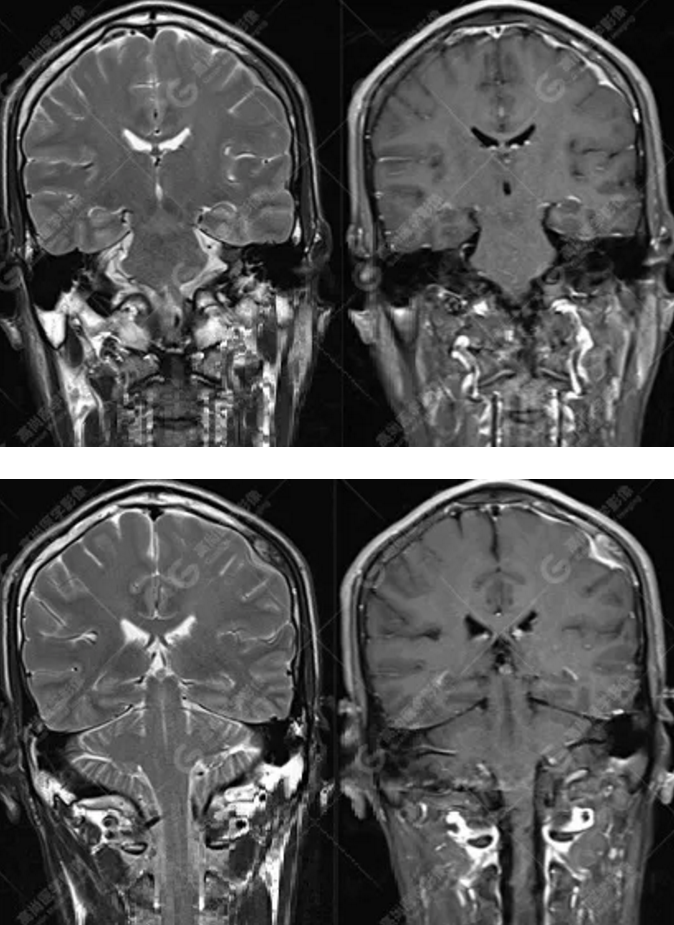

MR圖像

左側(cè)額頂部顱骨骨質(zhì)破壞并相鄰硬腦膜增厚強(qiáng)化,考慮Rosai Dorfman?。≧DD)可能,需與朗格漢斯細(xì)胞組織細(xì)胞增生癥鑒別。

典型的RDD在MRI上T1WI 呈等信號(hào),T2WI及 DWI為等-低信號(hào),增強(qiáng)掃描多為明顯均勻強(qiáng)化,多伴有腦膜尾征,部分病例伴有不同程度的腦水腫。T2WI 像 RDD 病灶中出現(xiàn)聚集的低信號(hào)影及 CT檢查沒有鈣化是 RDD 的特征性影像學(xué)表現(xiàn)。